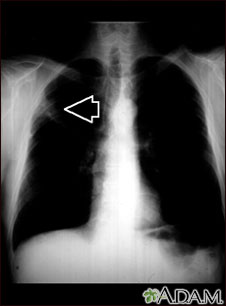

This picture is a chest x-ray of a person with a lung mass. This is a front view, where the lungs are the two dark areas and the heart and other structures are visible in the middle of the chest. The x-ray shows a mass in the right upper lung, indicated with the arrow (seen on the left side of the picture).